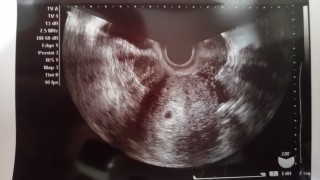

胎嚢のみ確認できました。 前回生理開始日から6週だと思っていたら「現在5週です」との事。 1週間前の診察では影も形も見えず、子宮外妊娠かも…と思っていたので安心しました。

最終月経開始日1/18。3/6に陽性。3/7胎嚢見えず。3/15に胎嚢確認、7ミリ。次は2週間後に診察!心拍確認できますように!